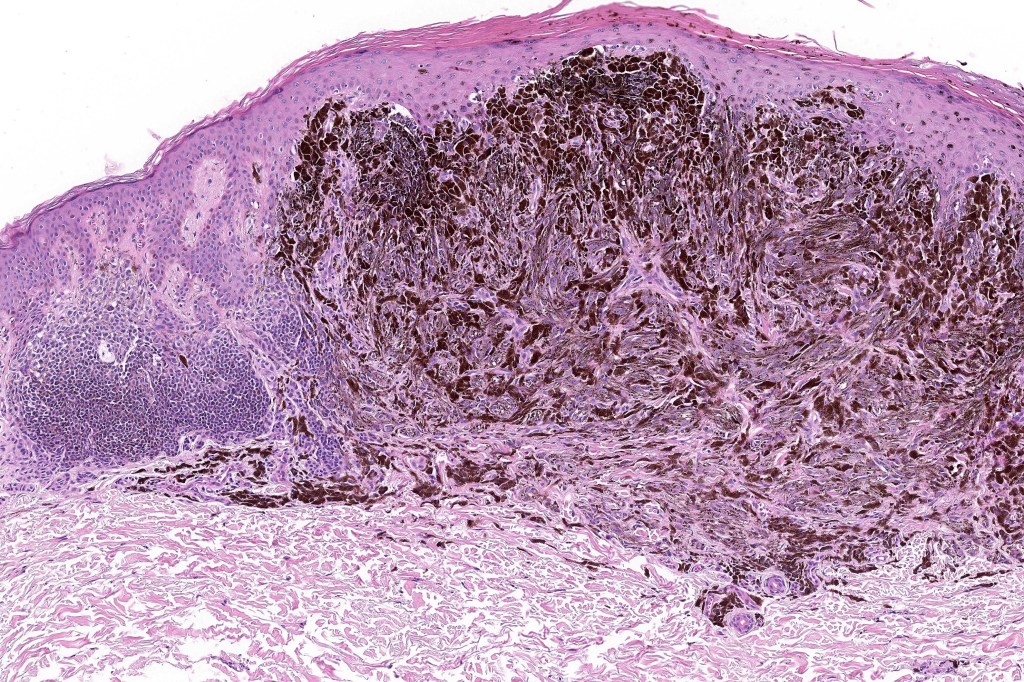

Combined common & deep penetrating nevus